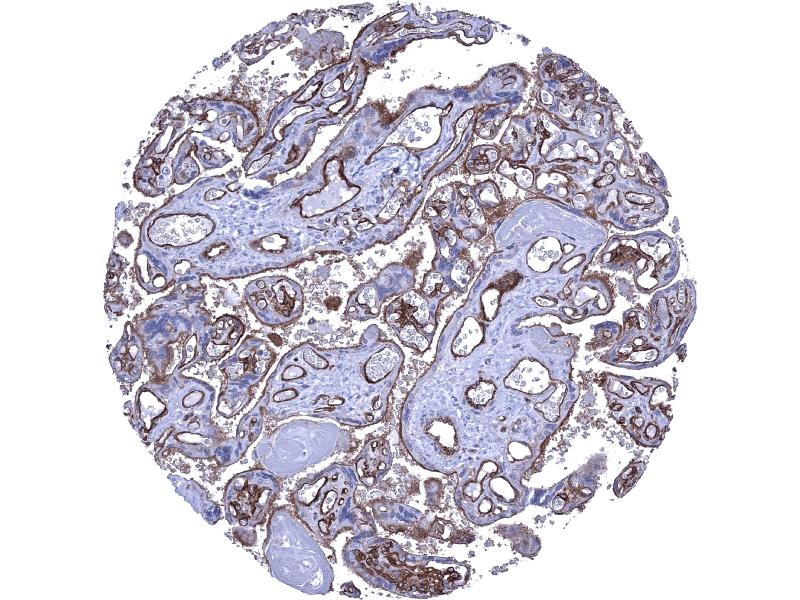

THBD 适用: 人 WB, IHC, IF 宿主: 兔 Polyclonal unconjugated

产品编号 ABIN1683026

100 μg (More quantities available)

发货至: 中国

获取报价